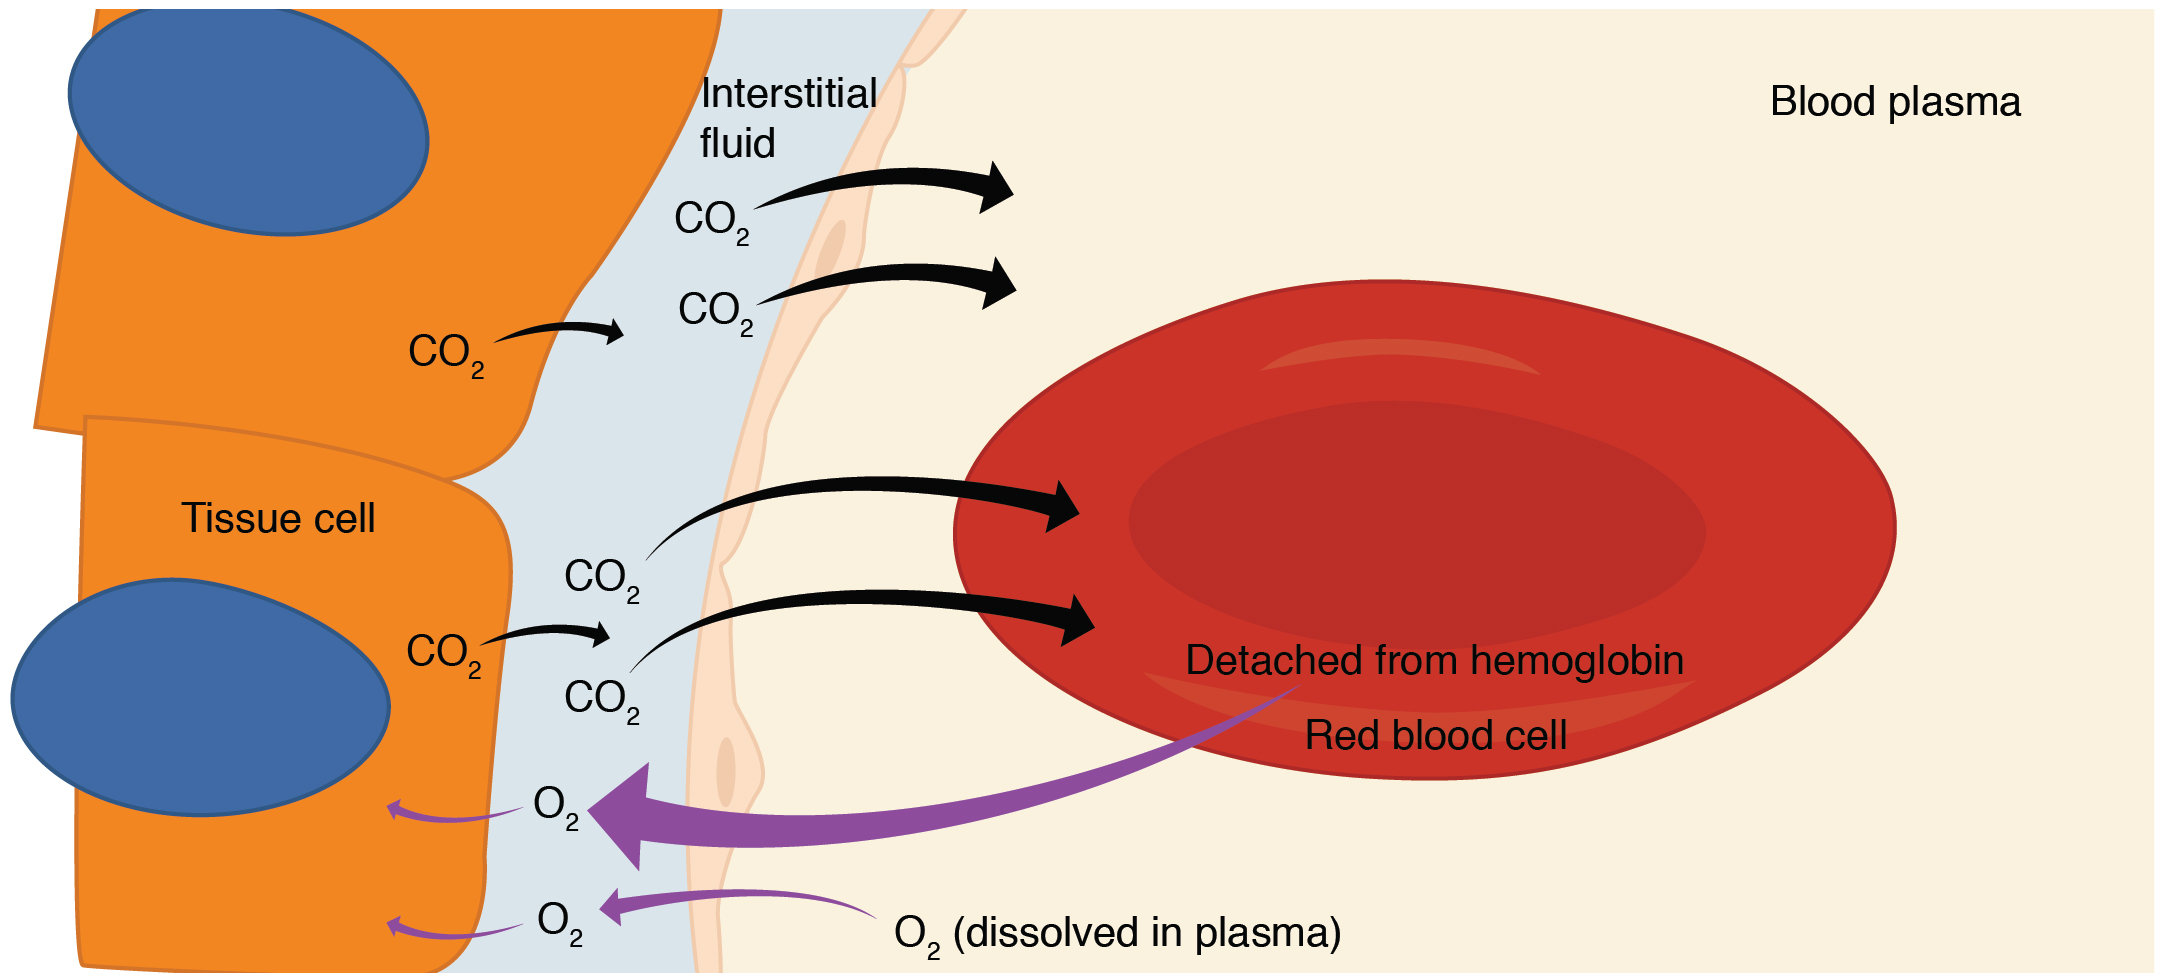

Hypoxemia – is a condition involving abnormally low blood oxygen levels. It can lead to bluish skin, difficulty breathing and fast heart rate. Apart from sleep apnea and higher altitudes, hypoxemia can be also be caused by many underlying illnesses, mainly lung and heart related especially in conditions of low environmental oxygen, diffusion impairment, hypoventilation, right -to left atrial shunting (image below).

Hypoxia – is a condition involving abnormally low levels of oxygen in body tissues. It can lead to bluish skin, confusion, difficulty breathing, restlessness and fast heart rate. Hypoxia is different to hypoxemia as hypoxia is low oxygen levels in tissues whereas hypoxemia is low oxygen levels in blood.